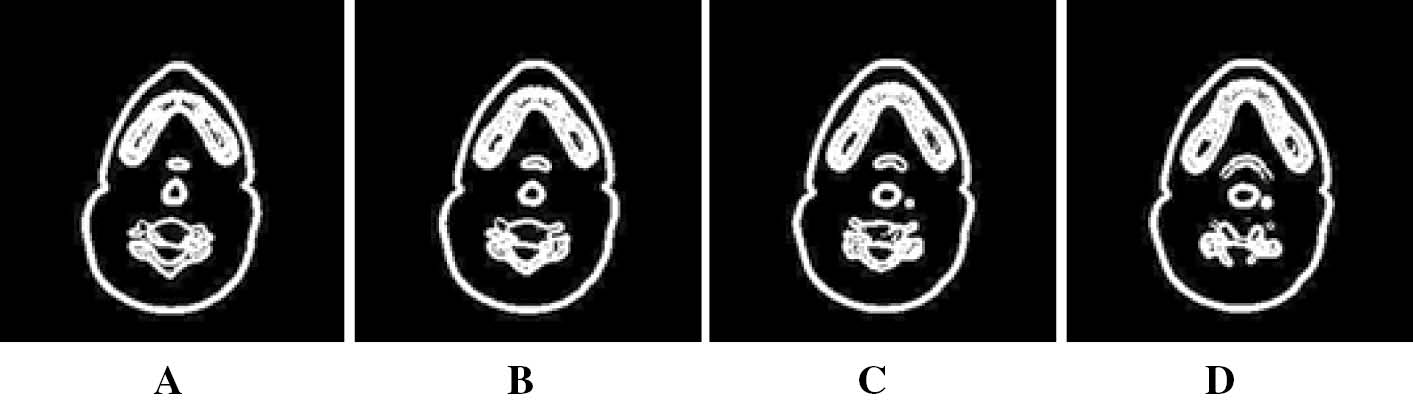

This study employs a collection of normal human head CT images taken from specialized and well-equipped scan center utilizing Siemens SOMATOM Sensation 64-slice CT scanner (Forchheim, Germany) (cardiac imaging with rotating time of 0.33 s and isotropic spatial resolution of 0.24 mm). The original images are in DICOM format, and we have chosen a test data of 100 slices for our implementation out of which the first four slices are shown in Figure 2. The current implementation was performed in MATLAB R2009b with Intel® Pentium® CPU B940 at 2 GHz, 4 GB RAM for an image size of 256∗256.

Axial cross section of a human head CT-(A–D) corresponds to the first four slices respectively in DICOM format.